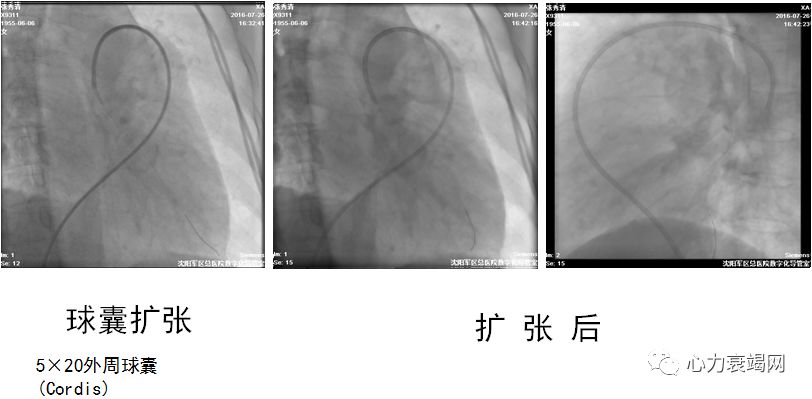

活动后胸闷、气短8年于2016年7月20日入院

确诊CTEPH 8年,拒绝肺动脉内膜剥脱术,服用华法林2年

球囊扩张术后肺动脉压力由120/48(72)mmHg降至90/32(51)mmHg